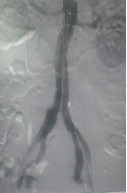

术后左髂内动脉通畅

手术在全麻下进行。团队通过双侧股动脉入路,同时建立左桡动脉通路以确保精准输送。首先超选肠系膜下动脉并完成弹簧圈栓塞;随后依次释放腹主动脉主体支架、右侧髂支及IBD主体支架;最后经桡动脉路径将覆膜支架精准送入左髂内动脉并释放。术中球囊后扩张各连接处,最终造影显示:腹主动脉、双侧髂总、髂外及髂内动脉均通畅,无内漏,瘤腔完全隔绝——手术圆满成功。

术后第二天患者即可下床活动、正常进食;阴茎勃起功能未受影响。术后第三天顺利出院。随访至今,患者无不适,性生活恢复正常,对手术效果高度满意。